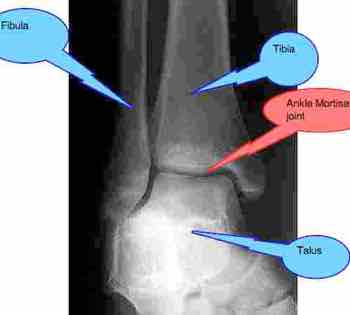

Diagram of ankle anatomy

The sharp pain within the ankle joint is more complicated; it may just be a chronic subluxation in the ankle mortice or subtalar joints, both of which cause sharp stabs of pain. That responds well to chiropractic adjustments.

3. Subluxate bones in the ankle, usually the mortise or subtalar joints.